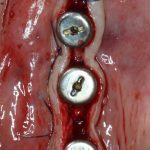

Изоляция области аутографта и имплантатов барьерной мембраной.

Перекрывать костный блок барьерной мембраной или оставить так? По этому вопросу есть много мнений. Между тем, в публикации по методике есть ясное показание, когда это требуется.

Конкретно в этом клиническом случае между костным аутотрансплантатом, ложем и имплантатами есть пустое пространство. Если его не изолировать от мягких тканей, они прорастут и осложнят интеграцию аутографта. Поэтому я решил перекрыть костный блок барьерной мембраной, пусть это делает хирургическую операцию немного дороже.

— ты знаешь, что барьерная мембрана может выполнять две функции, каркасную и изолирующую. Первая функция требует обязательной фиксации и натяжения, вторая — нет. В нашем случае «каркасом» регенерата является костный блок, а барьерная мембрана нужна только для изоляции. Поэтому она не требует натяжения и фиксации пинами.

После я внимательно проверил, что костный блок и имплантаты полностью перекрыты. Теперь рану можно ушивать.